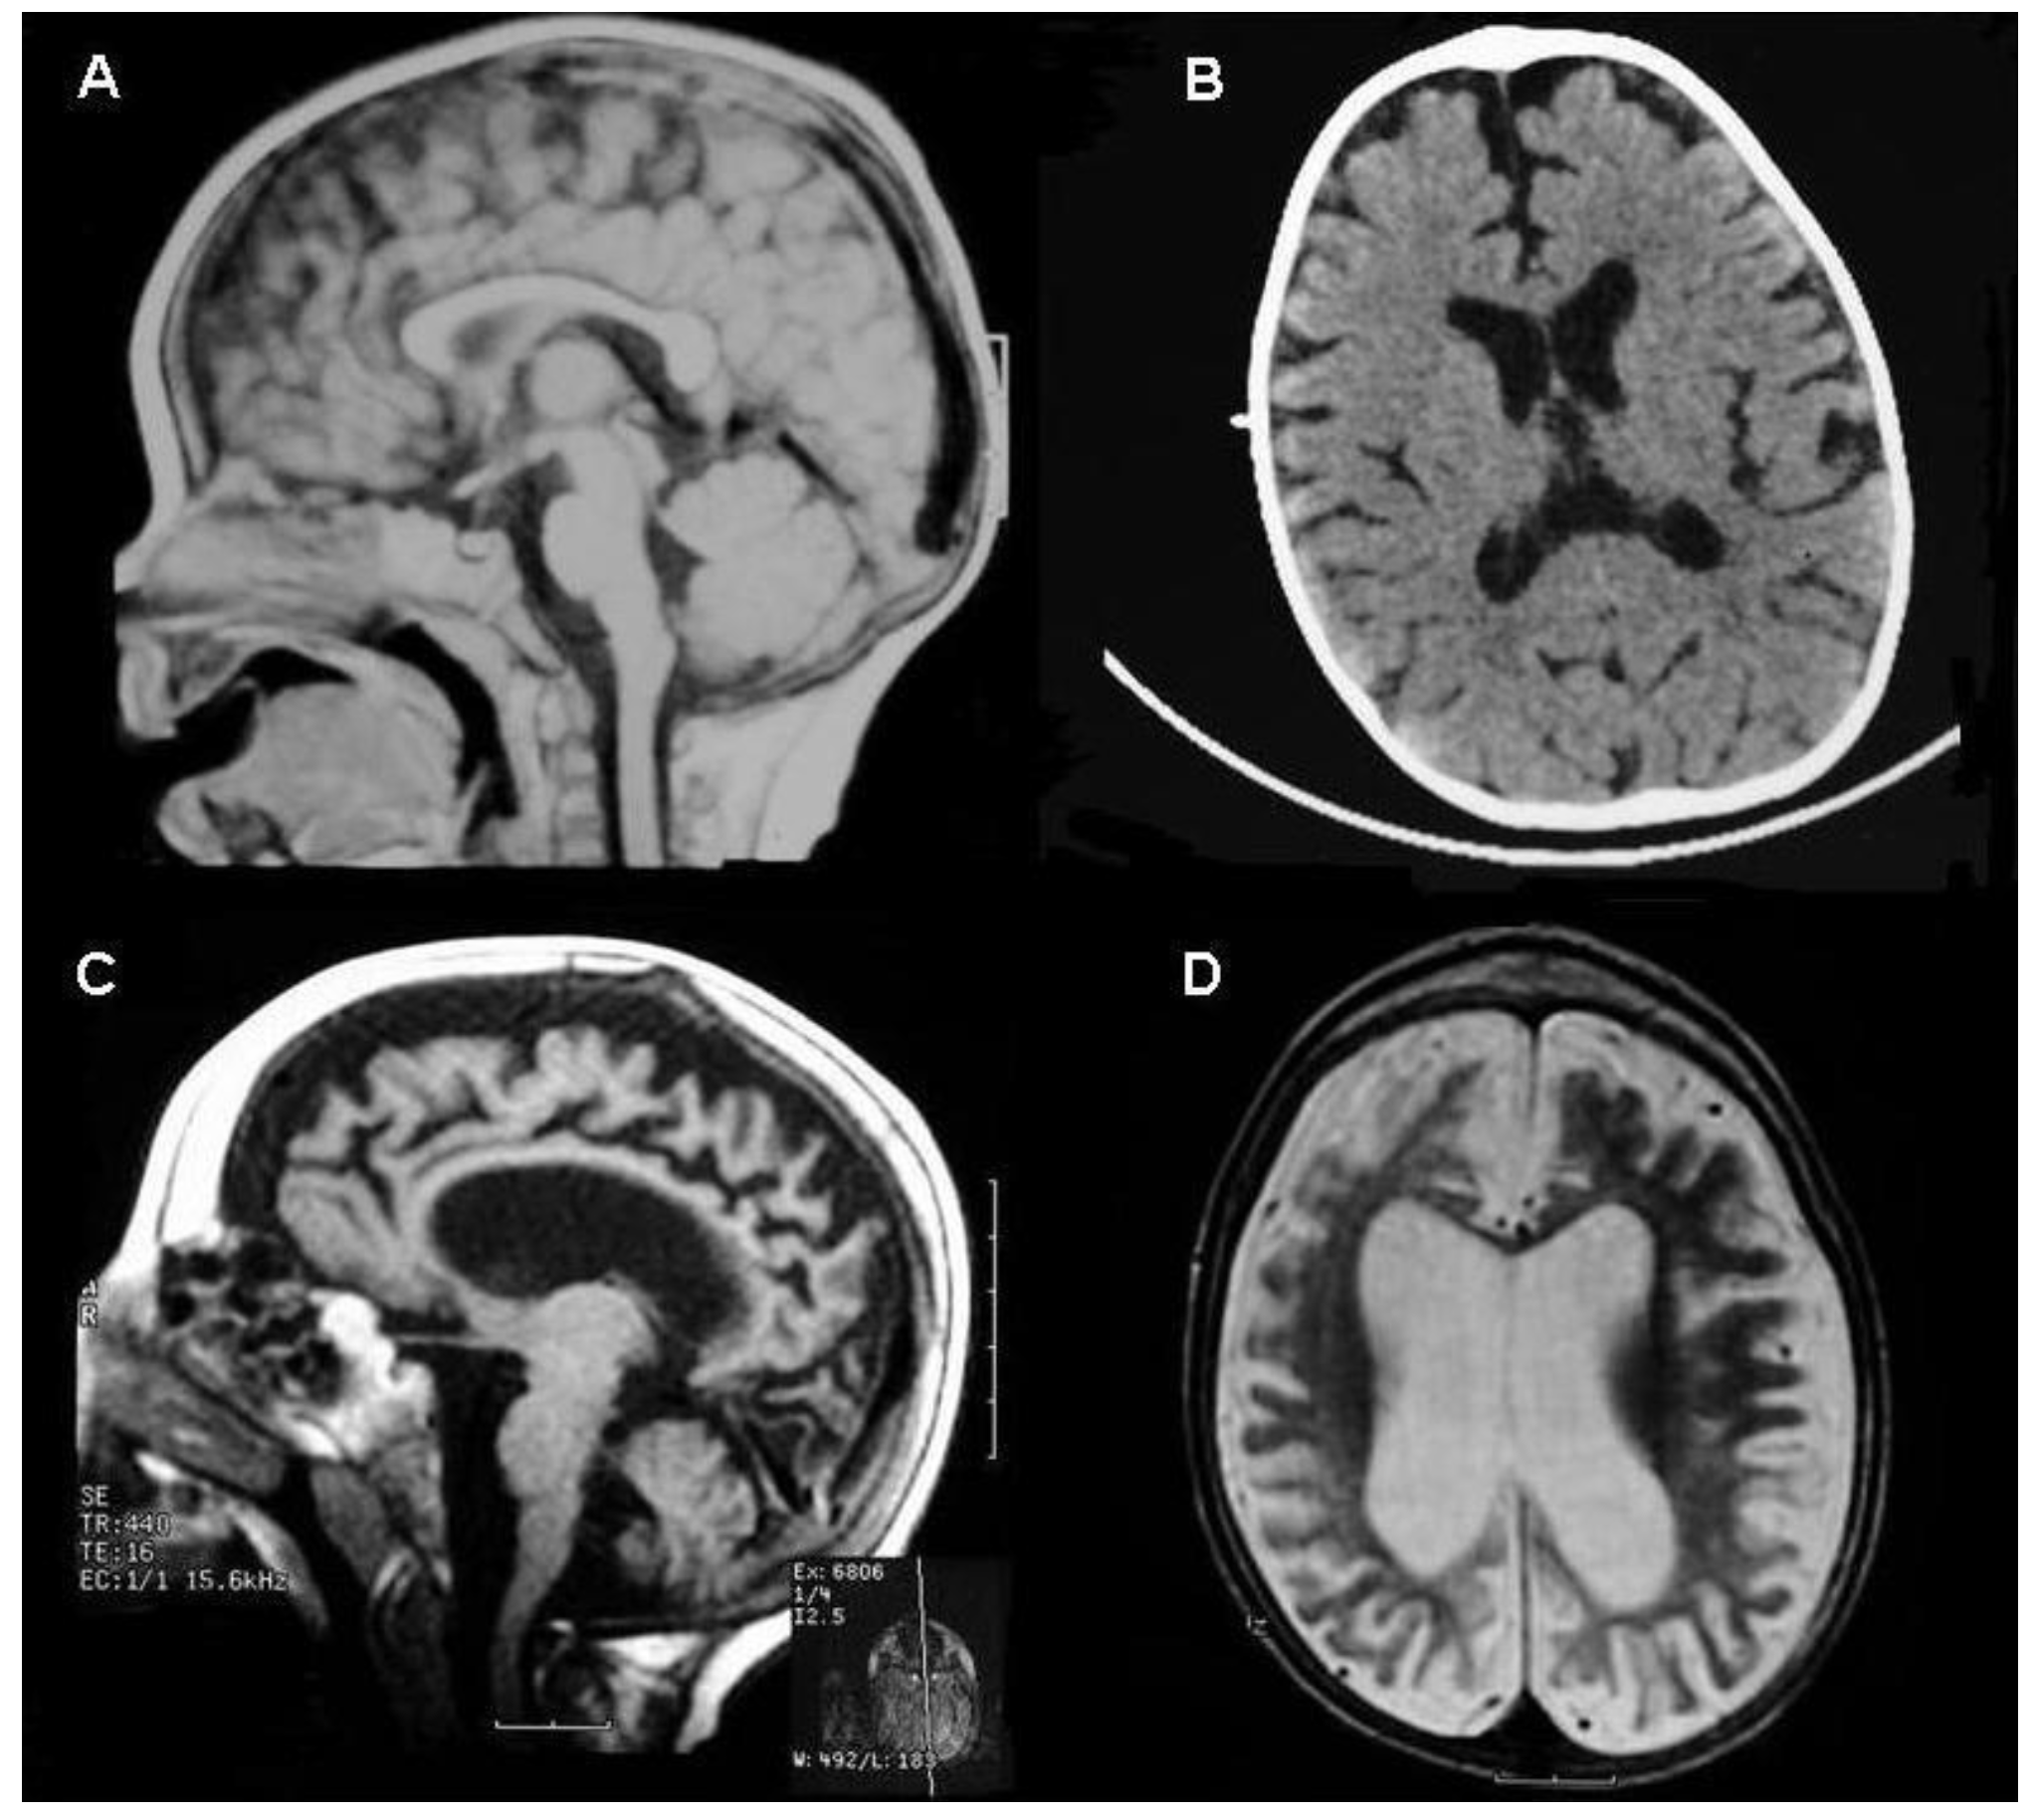

2. Case Report